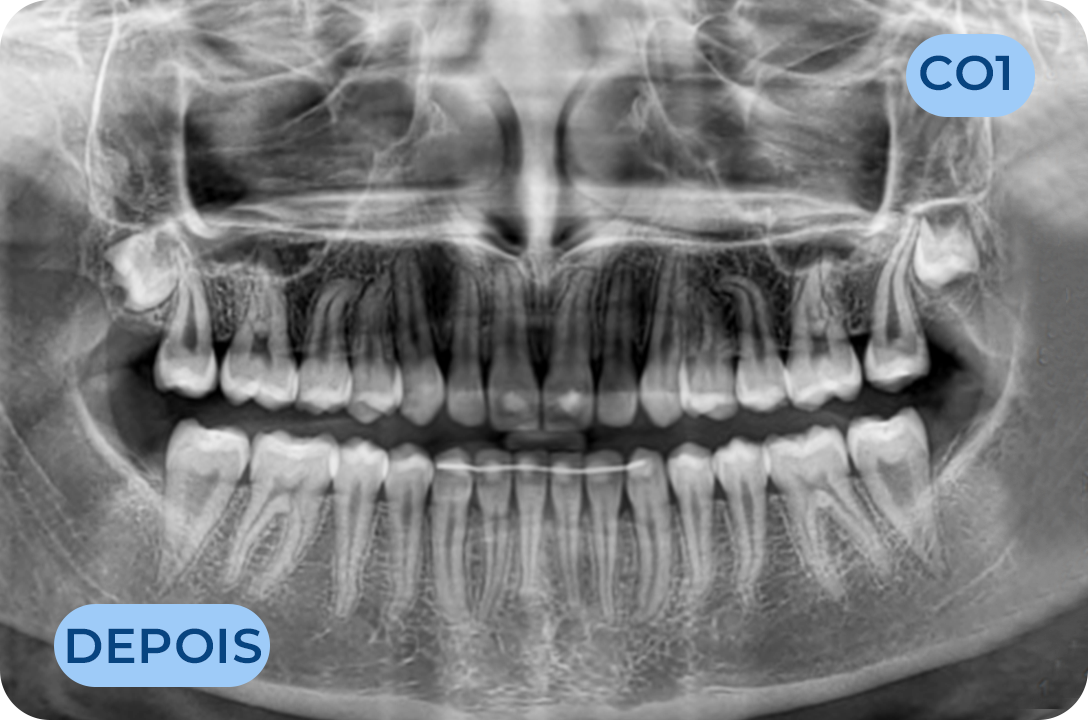

Ortodontia

É a especialidade da Medicina Dentária que se debruça sobre o estudo e correção das más posições dentárias e dos maxilares. Atualmente é possível tratar pacientes de todas as idades, no entanto a 1ª consulta deve ser realizada ainda na infância para intercetar eventuais problemas de desenvolvimento esquelético e funcional.

Cirurgia Oral

Área da medicina dentaria que diagnostica e trata as lesões e anomalias dos dentes, tecidos moles e estruturas anexas aos maxilares. A extração de dentes irrecuperáveis, dentes inclusos, supranumerários, frenectomias (eliminação dos freios), biopsias, exérese de quistos e outras lesões dos tecidos orais, fazem parte do seu vasto campo de execução.